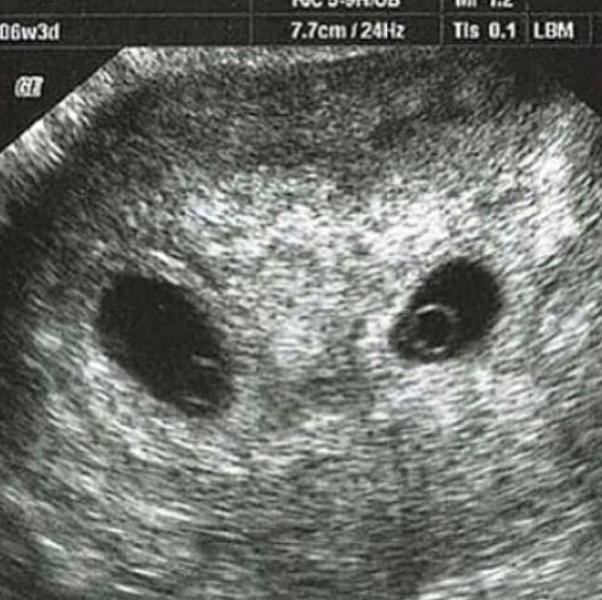

Эти два маленьких комочка лежат здесь на протяжении 6 недель, но мы ничего не знали😱

конечно сначала нас охватил шок 😨😳 но мы все равно безумно рады 🙏🙏🙏 особенно от того,что их двое👼👼

Мы ещё не узнали их пол, но уже безмерно счастливы 😍😍😍